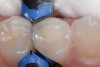

2. Side-by-side restorations placed with bulk-fill composite (Aura Bulk Fill, SDI) prior to removal of the sectional matrix on the distal aspect of tooth No. 12. A sectional matrix was first placed on the mesial aspect of tooth No. 13 and the restorative material placed and contoured prior to filling the preparation on tooth No. 12.

Figure 2